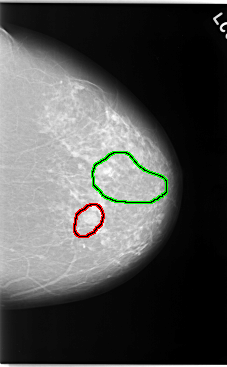

FILE: C_0044_1.LEFT_CC.OVERLAY TOTAL_ABNORMALITIES 2 ABNORMALITY 1 LESION_TYPE MASS SHAPE OVAL MARGINS CIRCUMSCRIBED ASSESSMENT 3 SUBTLETY 5 PATHOLOGY BENIGN TOTAL_OUTLINES 1 BOUNDARY ABNORMALITY 2 LESION_TYPE CALCIFICATION TYPE FINE_LINEAR_BRANCHING DISTRIBUTION SEGMENTAL ASSESSMENT 5 SUBTLETY 4 PATHOLOGY MALIGNANT TOTAL_OUTLINES 1 BOUNDARY |